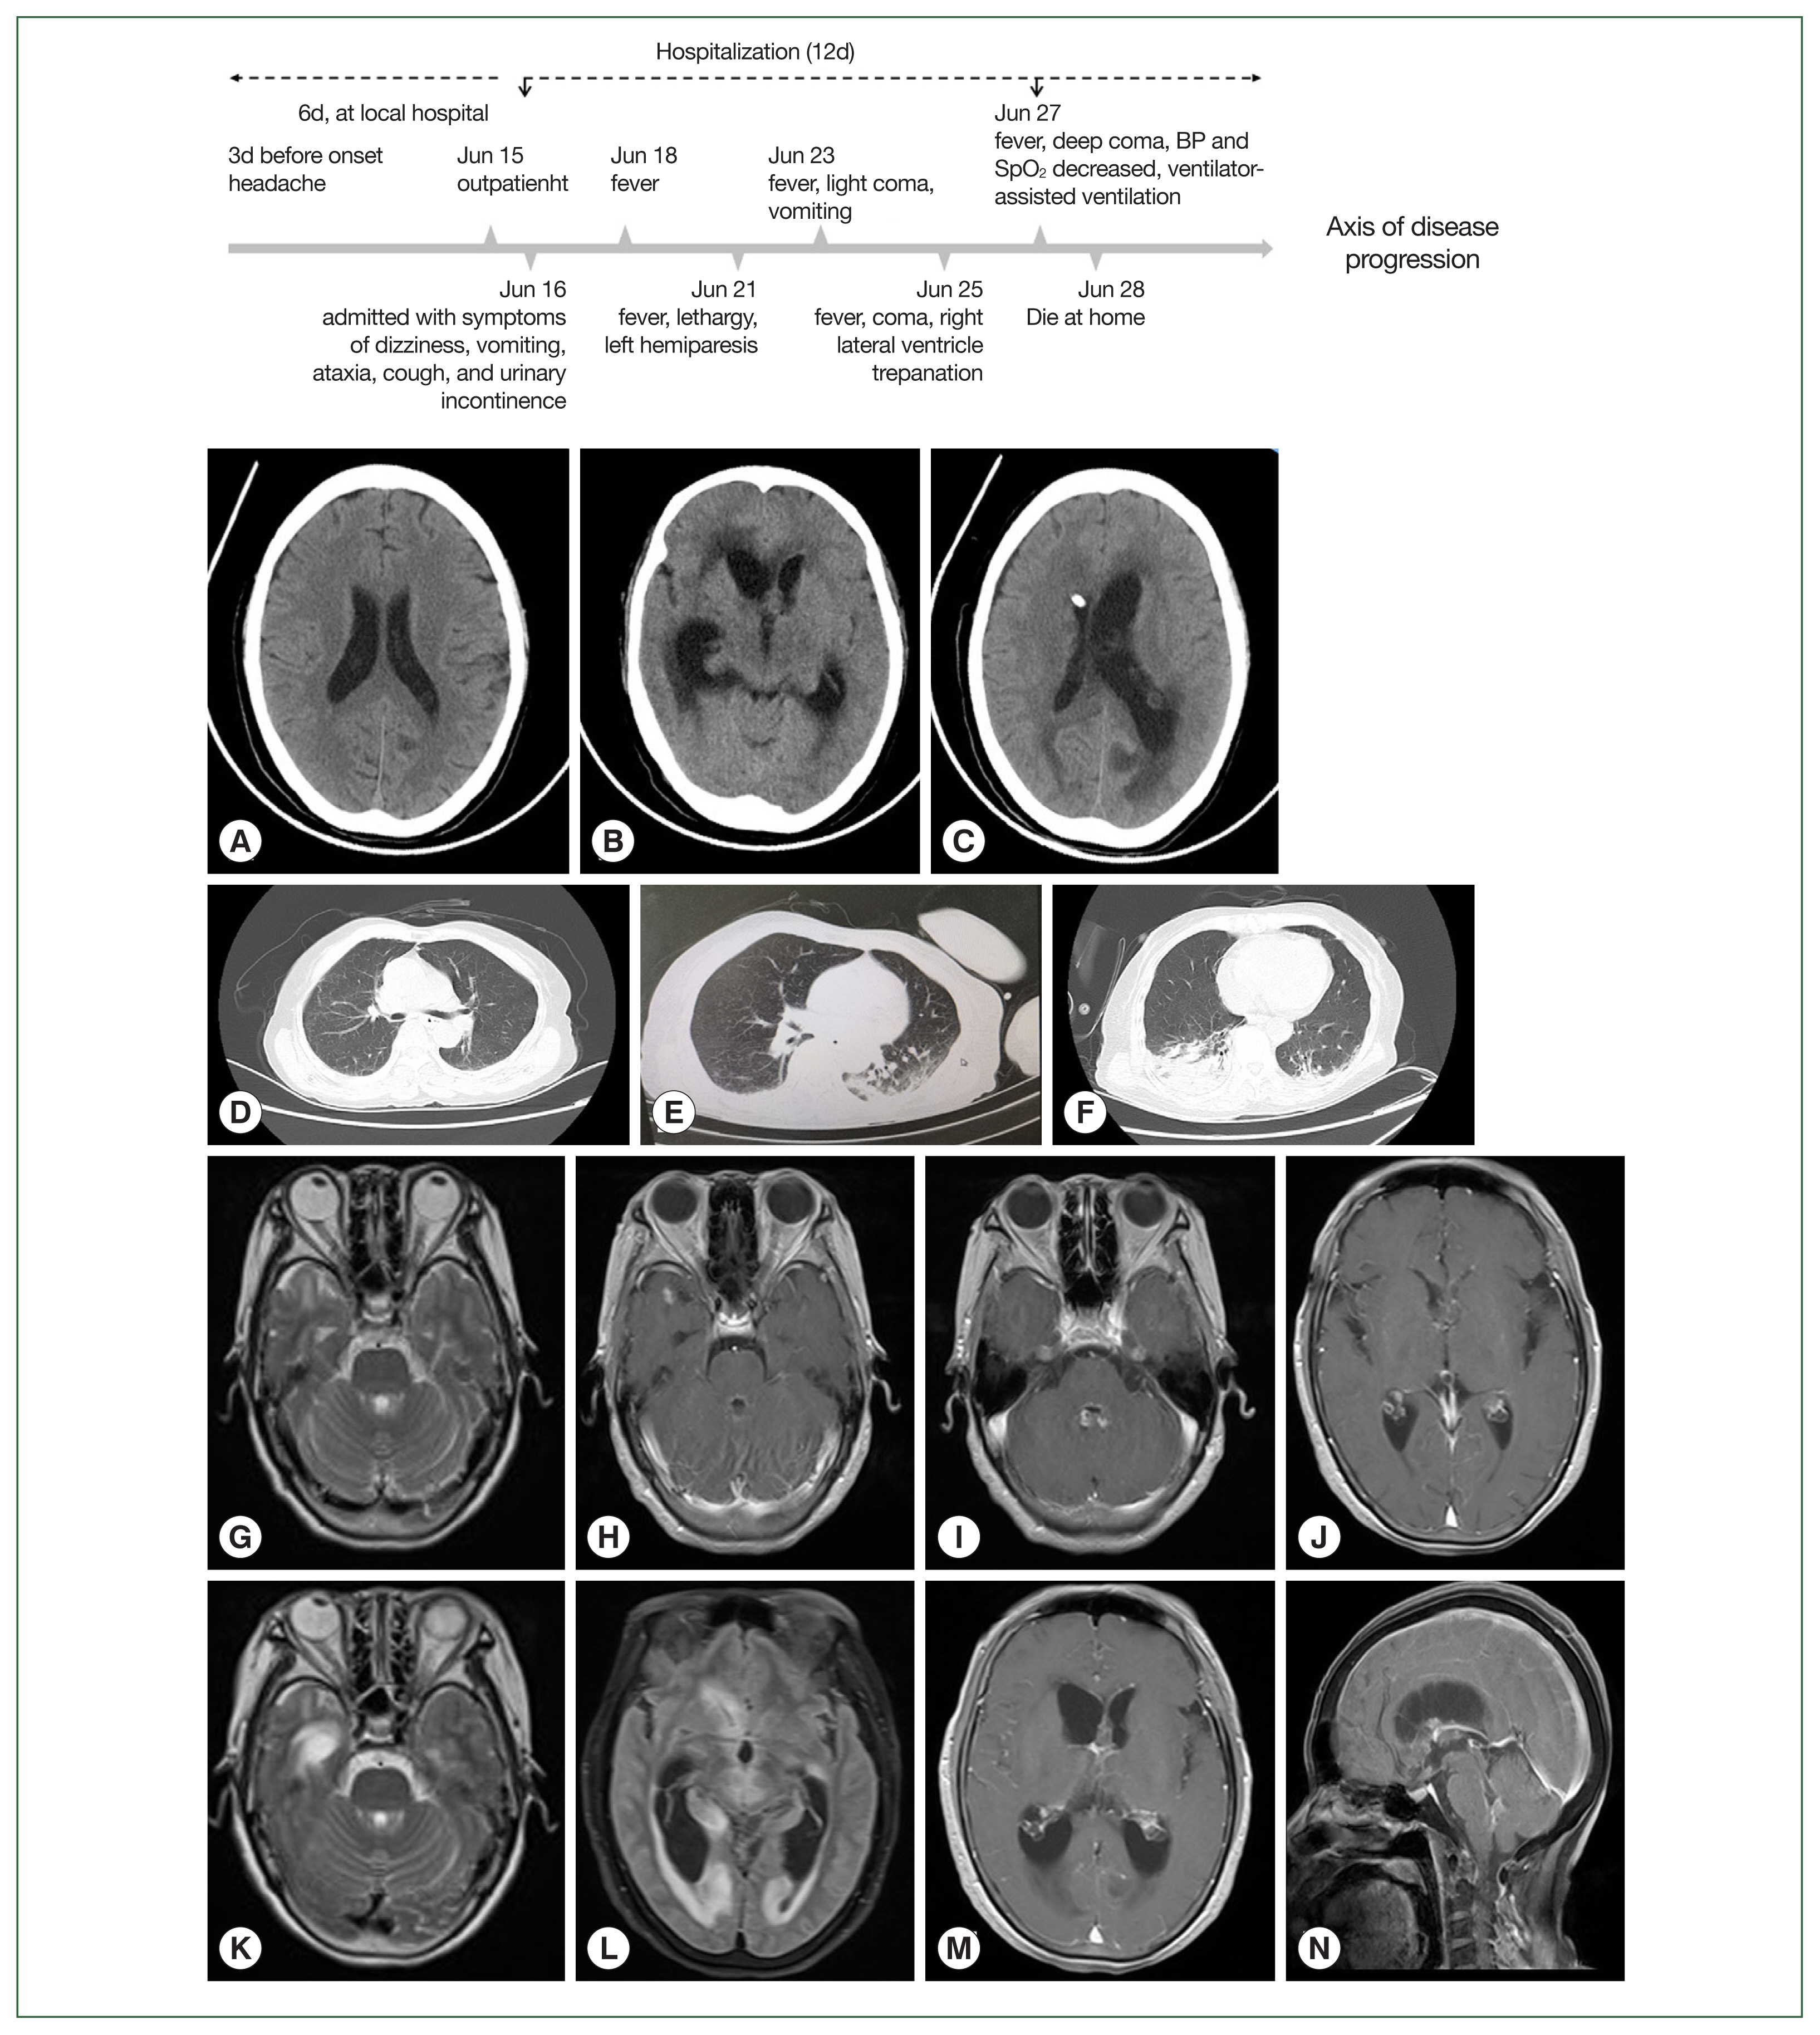

Balamuthia mandrillaris amebic encephalitis (BAE) can cause a fatal condition if diagnosis is delayed or effective treatment is lacking. Patients with BAE have been previously reported in 12 provinces of China, with skin lesions being the primary symptom and encephalitis developing after several years. However, a significantly lower number of cases has been reported in Southwest China. Here we report an aggressive BAE case of a 64-year-old woman farmer with a history of skin lesions on her left hand. She was admitted to our hospital due to symptoms of dizziness, headache, cough, vomiting, and gait instability. She was initially diagnosed with syphilitic meningoencephalitis and received a variety of empirical treatment that failed to improve her symptoms. Finally, she was diagnosed with BAE combined with amebic pneumonia using next-generation sequencing (NGS), qRT-PCR, sequence analysis, and imaging studies. She died approximately 3 weeks after the onset. This case highlights that the rapid development of encephalitis can be a prominent clinical manifestation of Balamuthia mandrillaris infection.